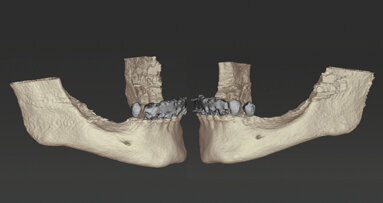

Paziente donna, di 71 anni, non fumatrice, in un buono stato di salute generale e nutrizionale si presenta con molteplici restauri protesici nella zona mascellare, composti da ponti e corone singole posizionate in tempi diversi. La mandibola rivela una tenuta protesica insufficiente. Il dente 43 è stato distrutto, sotto la corona, da una carie e ha subito un trattamento del canale radicolare (Fig. 1). La paziente ha richiesto ora la riabilitazione con una protesi fissa. La conseguenza di anni di utilizzo di protesi rimovibili, ha fatto sì che la mandibola risentisse di un problema di atrofia/riassorbimento di classe V-VI sulla destra e di classe IV-Cawood sulla sinistra1.

È stata discussa con la paziente la possibilità di un aumento osseo con materiale autologo prelevato dalla regione retromolare dei rispettivi lati e un successivo impianto. La paziente ha quindi richiesto una radiografia 3D preoperatoria (Fig. 2) per chiarire la necessità di questa procedura. È stata consigliata, dopo l’aumento, una pianificazione tridimensionale del trattamento implantare con coDiagnostiX (Dental Wings) per il posizionamento dell’impianto e un ripristino immediato tramite Multi-Base Abutments (Straumann).